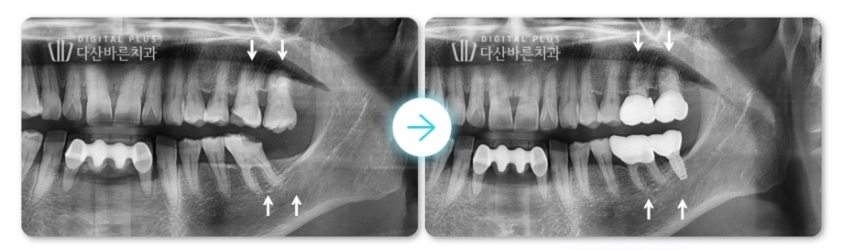

<최종 치료 전후 사진>